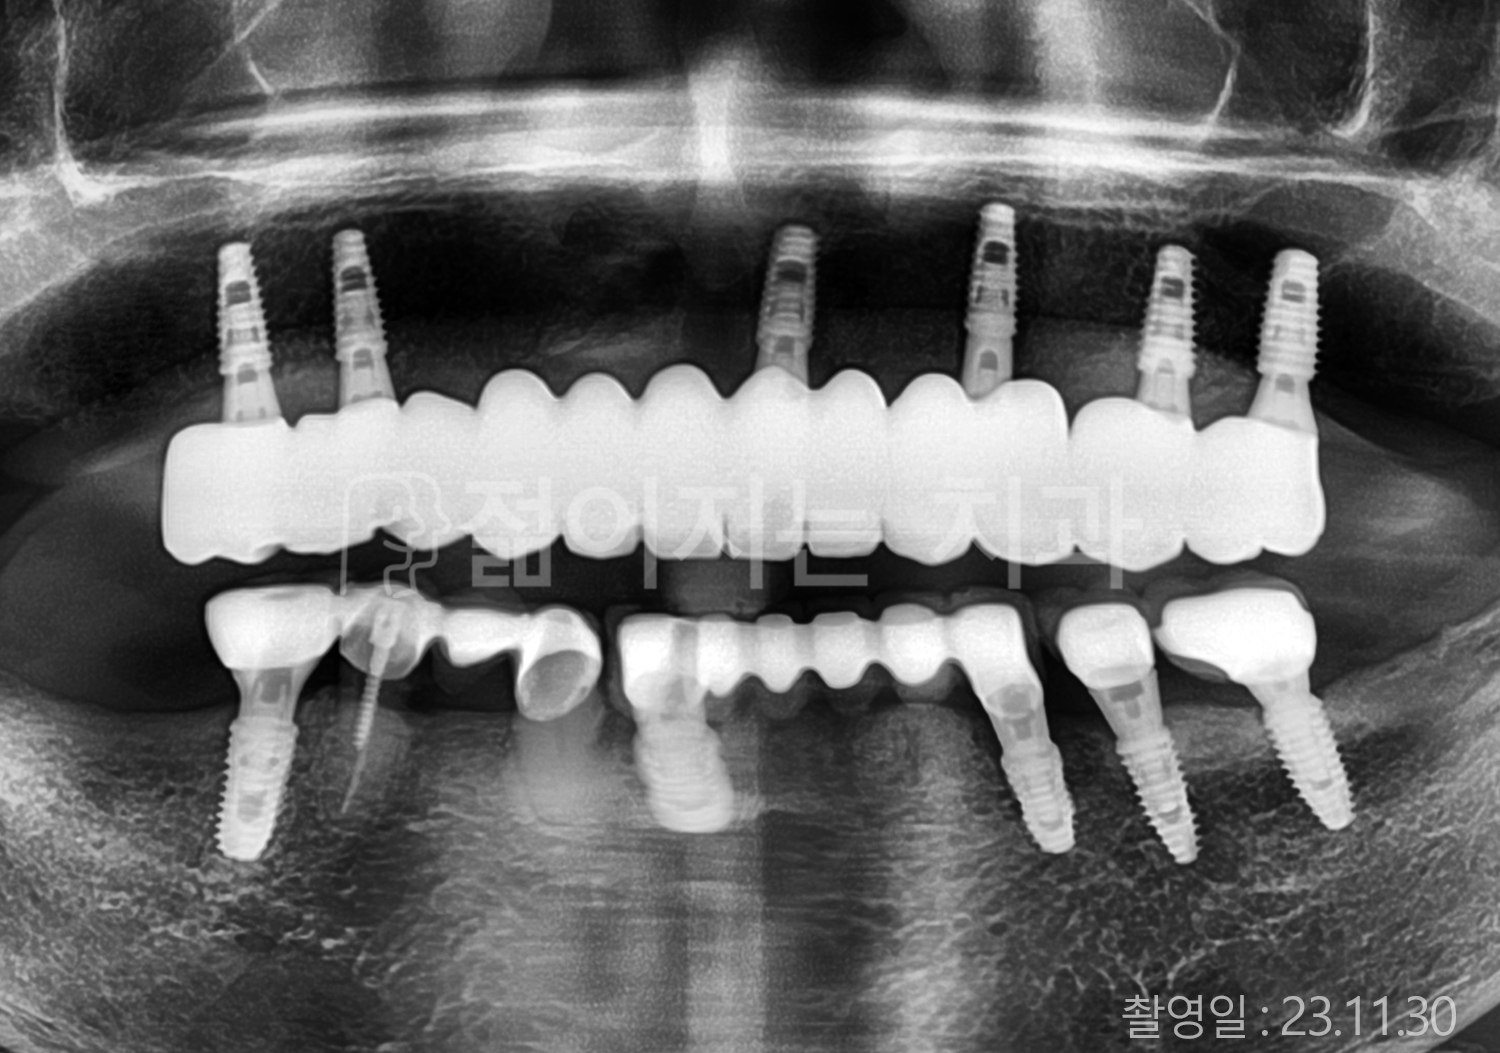

• 60대 고혈압, 고지혈증 전체치아 10개 이상 임플란트

• 70대 전체치아 10개 이상 임플란트

• 60대 전체치아 10개 이상 임플란트

• 50대 전체치아 10개 이상 임플란트

• 50대 고혈압, 고지혈증 전체치아 10개 이상 임플란트

• 60대 고혈압, 당뇨, 고지혈증 전체치아 10개 이상 임플란트

• 80대 고혈압, 당뇨, 골다공증 전체치아 10개 이상 임플란트

• 60대 고혈압 전체치아 10개 이상 임플란트

• 60대 고지혈증 전체치아 10개 이상 임플란트

• 60대 당뇨 전체치아 10개 이상 임플란트